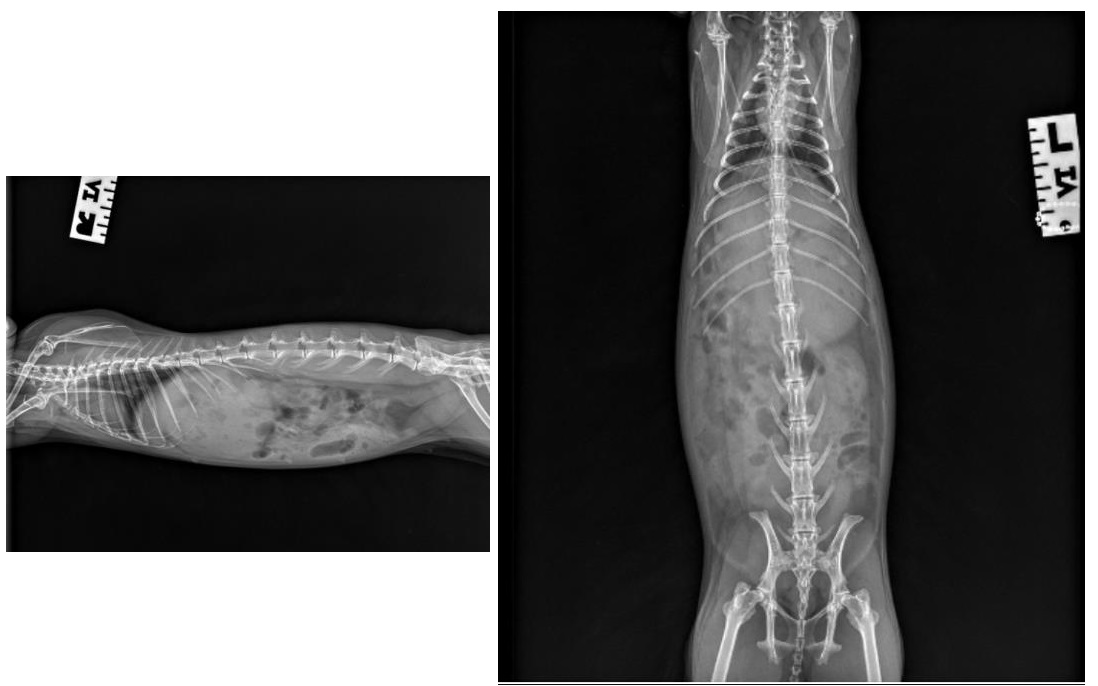

A series of diagnostics including radiographs, blood and urine tests were performed.

X-rays of Cotton Tail

The veterinary team diagnosed Cotton Tail with cystitis, likely caused by dietary factors. Her previous diet of alfalfa and fruit treats had contributed to urinary sludge formation, creating the perfect conditions for urinary inflammation.